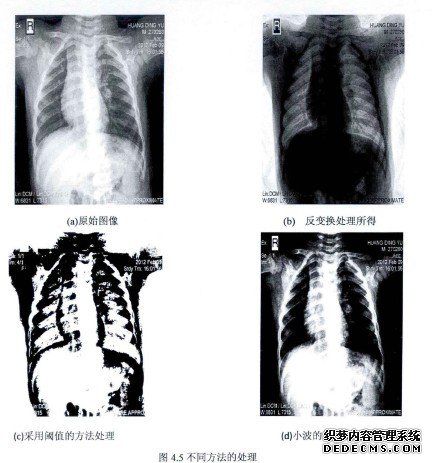

第四章医学图像增强算法

随着科技的快速发展,人们对图像的观察要求也越来越高,为了提高图像的视觉效果,人们在研究领域中也提出了各种各样增强图像的方法。目前图像增强技术已处于领先水平,并且在各领域中都得到了极为广泛的应用。在获得图像的过程中可能由于传输、存储等错误的操作造成图像的质量会得到下降,但是如今都可以通过一定图像处理的方法,使被测对象更加全面的、准确的特性被表达出来,从而有利于、清晰的认识与理解,因此图像增强技术显得尤为重要。许多图像与人类是密切相关的。医学图像中病变的研究与观察对人类的诊断是极为重要的。如今许多医学技术如CT、X射线等图像都是需要医生进行观察然后确定病症的,所以先进的医学图像处理技术能够更加准确的确定病情。但是往往由于在图像形成的过程中,可能会加有噪声等因素的影响会使得图像更为模糊,对比度表较低,不利于医生的诊断,因此对医学图像进行增强处理以及增强算法的研究有着重要的意义[26_28]。本章首先在理论的基础上介绍了增强算法的背景以及其分类,包括空间域图像和频率域两种形式的增强方法。然后以多尺度处理的方法为理论基础,对医学图像处理分别采用了小波变换以及Contourlet变换增强算法,并对两种算法做了较为深入的研究。